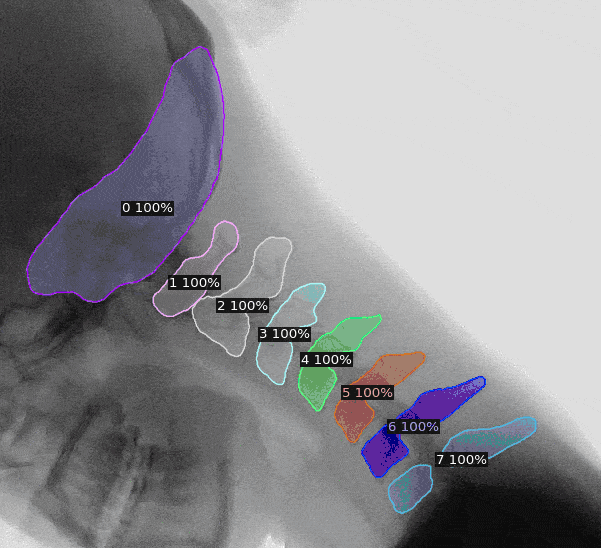

The use of artificial intelligence in diagnostic medical imaging has shown impressive accuracy and sensitivity in the identification of imaging abnormalities. Assisting healthcare professionals with detection, segmentation and classification, it can be of immense value for screenings and precision medicine. Our AI for Health engineers used Generative Adversarial Networks to segment X-rays of lungs to detect Covid-19. They applied U-nets and mask-RCNN for instance segmentation of cervical vertebrae to predict patient developing hernia.